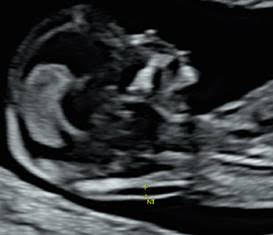

Sonographers are increasingly reporting service users taking overt and covert videos or photographs during antenatal ultrasound examinations. They have also highlighted concerns about social media posts informing service users that they have a right to video examinations and staff on NHS property.